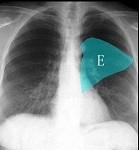

问题 如图所示正常胸部X线影像图像上,该英文字母所代表的肺段为 ( )

选项 A.内基底段 B.前基底段 C.外基底段 D.后基底段 E.背段

答案 E